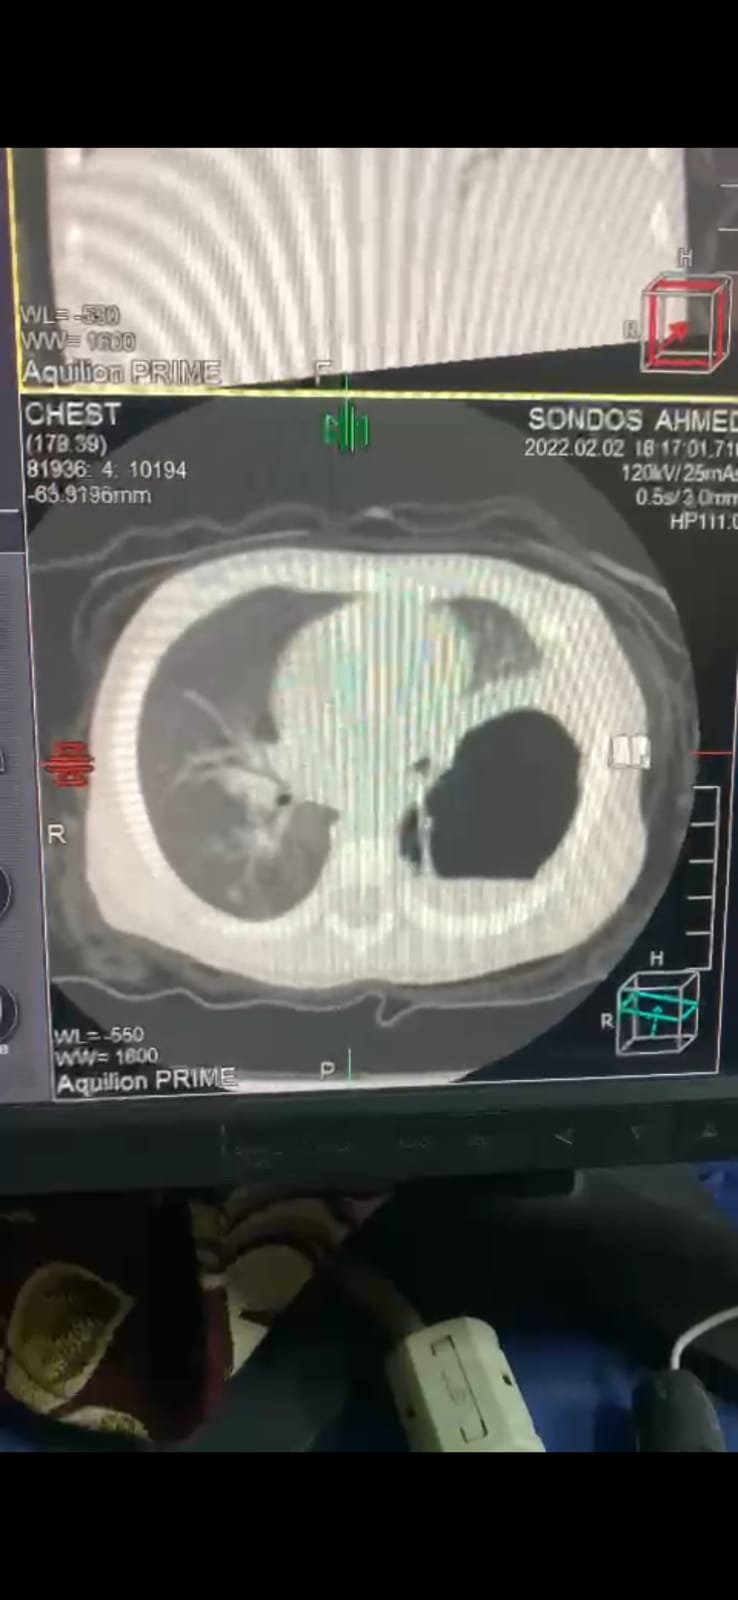

وأضاف عميد كلية الطب أن قسم الجراحة قام أيضا بإجراء عملية جراحية لفتاة تبلغ ١٦ عام تعاني من مرض السكر دخلت في غيبوبة سكر ووضعت على جهاز تنفس صناعي لمده أسبوع ثم أصيبت باختناق و توقف عضلة القلب و تم عمل إنعاش قلبي رئوي لها و تم نقلها فورا لغرفة العمليات و عمل استئصال لجزء من القصبة الهوائيه الضيق و إعادة توصيل القصبة الهوائية و حالتها الان مستقرة في عناية جراحة القلب و الصدر تمارس حياتها الطبيعية و مفصولة من أجهزة التنفس الصناعي .

كما قام باجراء عملية لحالة رجل يبلغ ٥٥ عام من محافظة قنا يعاني من ارتجاع شديد بالصمام الميترالي و تم إجراء عملية جراحة قلب مفتوح و تم استبدال الصمام الميترالي و خرج من المستشفى الجامعي خروج تحسن و يمارس حياته بشكل طبيعي وكذلك استقبل القسم حالة طفله تبلع من العمر عام و شهرين كانت تعاني من خراج وجود خراج بالفص السفلى من الرئه اليسرى و تسمك بالغاء البلوري ظلت محجوزة بالمستشفى لمده شهر كامل بعدما فشلت جميع محاولات العلاج الدوائي تم إجراء جراحة استكشاف للصدر و عمل تقشير الغشاء البلوري و استئصال الخراج مع الحفاظ على الفص السفلى من الرئه و خرجت المريضة من المستشفى الجامعي وتمارس حياتها طبيعية وسط اقرانها من الاطفال .